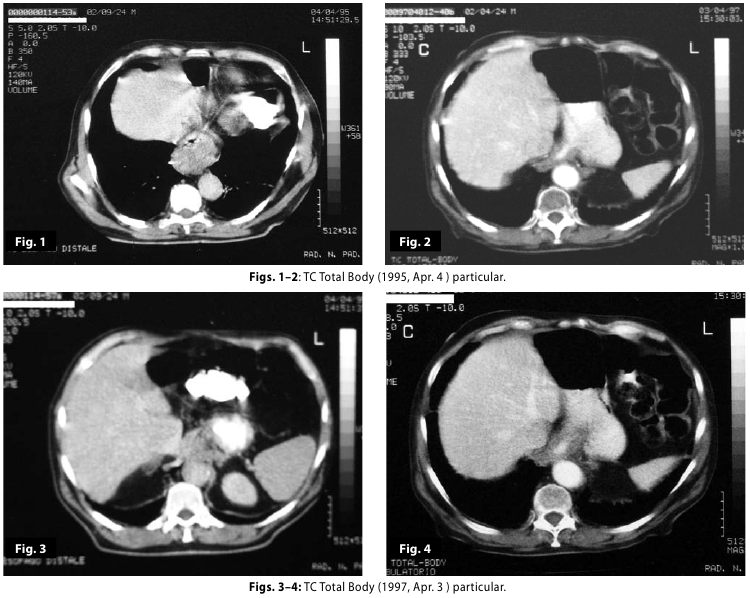

Figure1-2

Figure1-2-3-4